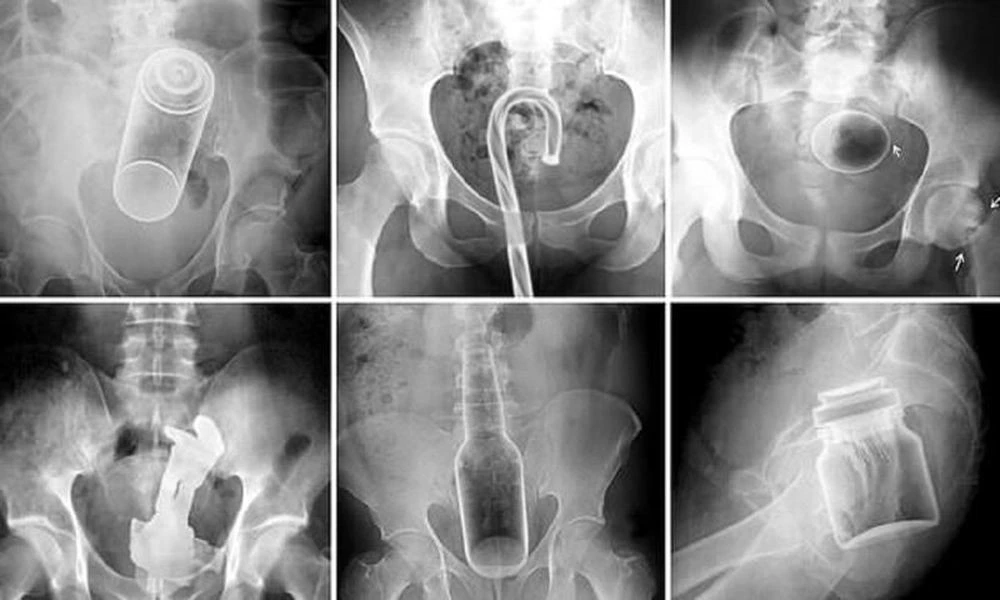

Експерти склали рейтинг речей, які застрягли у різних отворах людей у 2025 році (5 фото)

Медики поділилися списком предметів, які «випадково» застрягли у різних отворах любителів гострих відчуттів минулого року. Нижче перелік предметів із зазначенням отворів, у тому числі їх дістали.

Усі випадки — реальні звіти з бази Комісії з безпеки споживчих товарів, куди надходять анонімні дані щодо візитів до відділень невідкладної допомоги.

Пряма кишка:

- Пляшка з лубрикант;

- Цвяхи;

- Шурупи та цвяхи;

- "Пацієнт повідомляє, що помістив бейсбольний м'яч у пряму кишку, щоб подивитися, як це";

- аерозольний балон;

- Жувальна іграшка для собаки;

- Серветка для сушильної машини;

- «Відчував запор протягом 2 днів, зняв основу з машинки для бороди, загорнув у пластиковий пакет, вставив у пряму кишку, предмет застряг»;

- Жезл;

- Гумка для волосся;

- «Стурбується, чи не залишився невеликий вібратор у прямій кишці. Дівчина помістила його туди у п'ятницю»;

- Груша;

- Пластикова пляшка з засобом для чищення (повна рідини);

- "Повідомляє, що послизнувся в душі, і пляшка шампуню потрапила в пряму кишку";

— «Повідомляє, що був у душі, нудьгував, коли помістив пляшку шампуню у пряму кишку»;

- Стоматологічний зонд;

- Корок від вина;

- Утримувач для кукурудзяного качана;

— «Вчора ввечері був із дружиною, випив надто багато, прийшли додому п'яними, дружина вставила гумову секс-іграшку у пряму кишку пацієнта, витягти не вдалося»;

- Фломастер;

- Маркер;

- Іграшка;

— «Повідомляє, що 7-дюймовий дилдо потрапив надто глибоко у пряму кишку. Намагався витягти плоскогубцями. Плоскогубці теж застрягли»;

- Кульки;

- Кейс для фотоплівки;

- Ліхтарик на батарейках;

- «Пластикова вішалка всередині ануса. Вставив під час сексуальної активності. Відрізав зовнішню частину, щоб доїхати до приймального спокою»;

- Монета;

- сандалі;

- Дверна ручка;

- "Вставив лампочку в пряму кишку скляною стороною вперед, через ефект всмоктування лампочку затягнуло всередину";

- Ліхтарик;

- Вейп;

— «Можливе стороннє тіло у прямій кишці. Повідомляє, що помістила невеликий вібратор у пряму кишку, не пам'ятає, чи його витягувала, і не може знайти»;

- 2 олівці;

- Іграшка у вигляді кукурудзяного качана;

— «Повідомляє, що кілька годин тому використала анальну пробку, яка зламалася. Партнер намагався витягнути уламок пінцетом. Пінцет тепер теж застряг»;

- Гумова прокладка;

- Сирі макарони;

- Частина тримера для волосся;

— «Повідомляє, що у прямій кишці знаходиться вібруюче стороннє тіло. Був із дівчиною минулої ночі і мало що пам'ятає»;

- Окуляри;

- Камінь;

- Яйце;

— «Під час інтиму з дівчиною було вставлено прямокутний футляр від зубної щітки до прямої кишки, вдалося витягти лише половину»;

- Декілька секс-іграшок;

- Вібратор з котячою головою;

- Ділдо 45 сантиметрів;

- Ділдо 60 сантиметрів;

- «Повідомляє, що з 14:00 сьогодні в прямій кишці знаходиться 15-сантиметровий вібратор. Не пам'ятає, як помістив його туди.